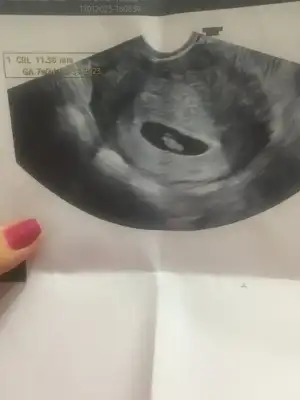

Sat 5 aralığa gore 6.haftamda olmam lazimdı. Bugun ilk kontrolume girdim kese gorundu ancak bebek daha gorunmuyor 4 yada maksimum 5. Haftandasin daha erken dedi 25inde tekrar gidecegım umarim boş gebelik degildir.

Sat 5 aralığa gore 6.haftamda olmam lazimdı. Bugun ilk kontrolume girdim kese gorundu ancak bebek daha gorunmuyor 4 yada maksimum 5. Haftandasin daha erken dedi 25inde tekrar gidecegım umarim boş gebelik degildir.

Yani ben cok anlayamadim buraya atilanlarda hafra gun olarak gozkuyordu ama ben goremedim kendiminkinde sende bakarmisin birdeHoşgeldin canım, benimde sat a göre 6 haftalıkken 5 haftalık çıktı doktorum geç döllenme dedi, ben kiloluyum insülin direnci var mı yok mu bilmiyorum ama diyet yaparken hamile kaldım devam et dedi doktor ama kilo söylemedi biraz pimpirikli bir doktora denk gelmiş olabilirsin daha yolun başındayız kafana yatmadıysa değiştir bence ayrıca ultrason kağıdı vermedi mi orada kaç hafta gözüktüğü yazıyor canım kese gözükmüş işte ne güzel

Ayrica cm yazanlar kese boyutumu acaba

Eklentiler

Evet yazmıyor seninkinde bence cm yazanlar kese evet canım doktorun makinesinden herhaldeYani ben cok anlayamadim buraya atilanlarda hafra gun olarak gozkuyordu ama ben goremedim kendiminkinde sende bakarmisin birde

Ayrica cm yazanlar kese boyutumu acaba